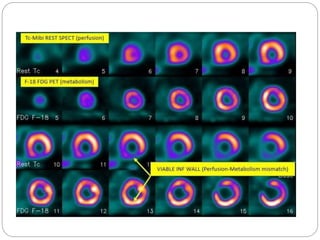

PET

FDG-PET (for viability)

• Based on the fact that myocardium utilizes glucose for

metabolism when under effect of ischemia (hence the

ischemic myocardium will show greater uptake than normal

cells)

• Under normal circumstances, it utilizes fatty acids for

energy

• Non-viable myocardium will not show any uptake

 PET viability is a unique modality in its ability to

evaluate myocardial tissue’s metabolic activity

utilizing intracellular-biochemical pathways

 It requires coupling of myocardial perfusion

data with myocardial metabolic assessment

using various radioactive tracers

 Cardiac PET uses N‐13 ammonia or

Rubidium‐82 (82Rb) to assess perfusion and

 F18‐Fludeoxyglucose (18F‐FDG) to evaluate

myocardial glucose metabolism

 At rest, healthy myocardium oxidizes free fatty

acids to produce ATP

 In the setting of myocardial ischemia, there

would be a shift of hibernating myocardial

metabolism from fatty acids to glucose with

upregulation of glucose transporters

Mismatch defect seen in the lateral wall with reduced perfusion and normal metabolic

Matched defect seen in the anterior wall with reduced perfusion and metabolic a